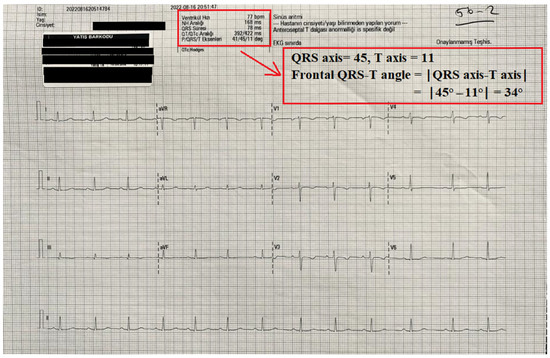

| Frontal QRS-T angle (°) Pre-operative Post-operative | 16.0 (7.8–34.3) 21.0 (12.0–34.0) | 24.0 (20.0–41.5) 34.5 (19.5–50.0) | 0.045 b 0.007 b |

| p = 0.056 e | p = 0.031 e |